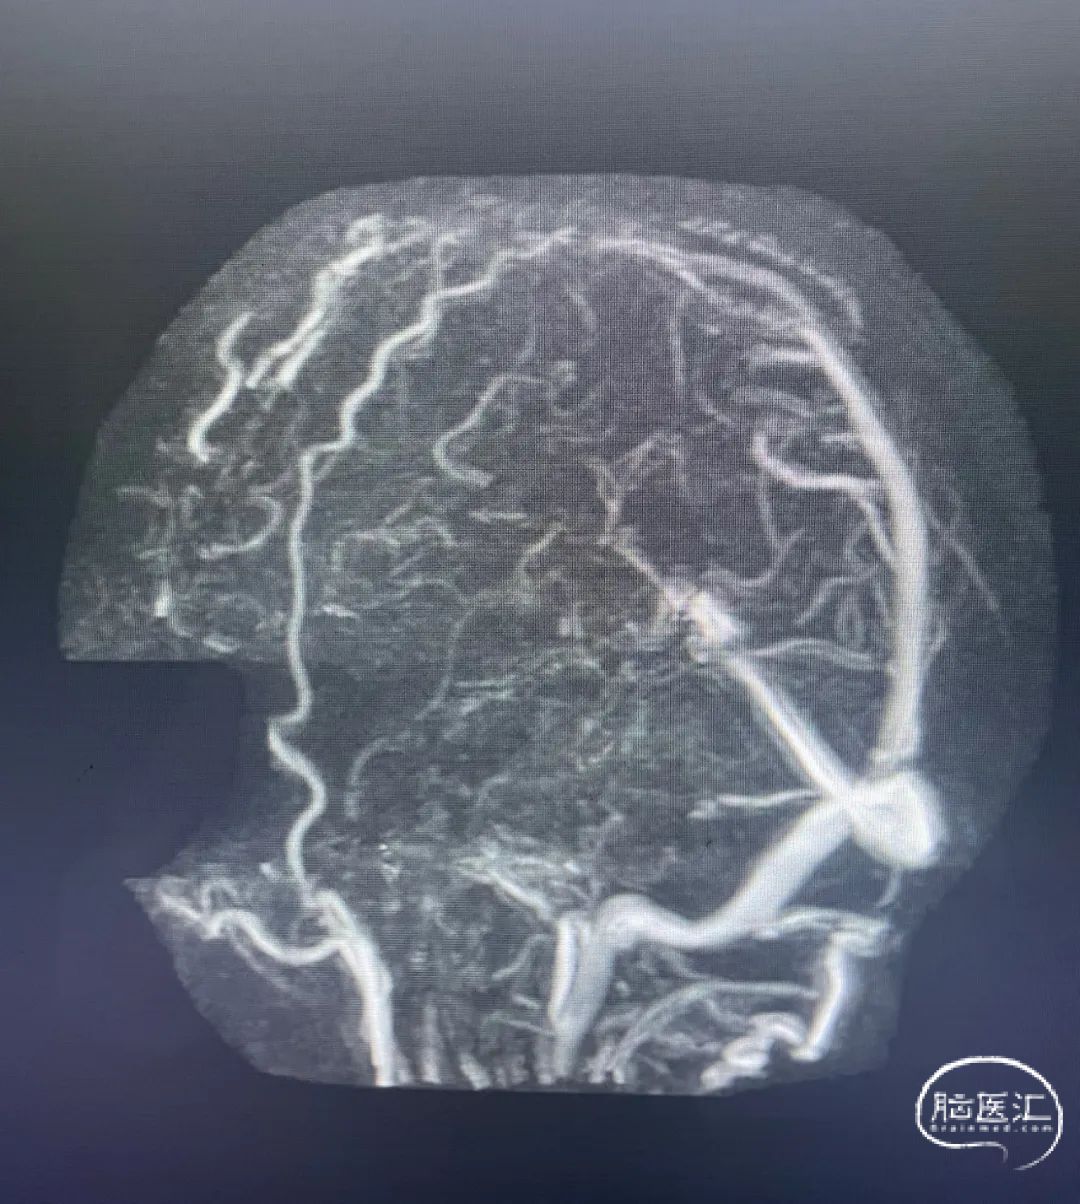

入院影像检查

MRA提示右侧大脑中动脉M1段局限性重度狭窄。

CTA提示右侧大脑中动脉局部充盈缺损。

入院后DSA提示右侧大脑中动脉充盈缺损,考虑夹层可能大。